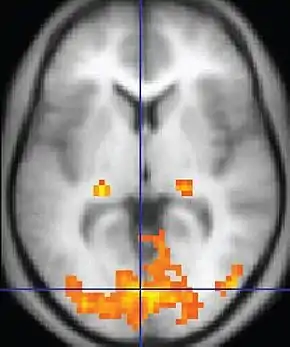

Functional MRI (fMRI)Blood-oxygen-level dependent imagingBOLDChanges in oxygen saturation-dependent magnetism of hemoglobin reflects tissue activity.[38] Localizing brain activity from performing an assigned task (e.g. talking, moving fingers) before surgery, also used in research of cognition.[39]